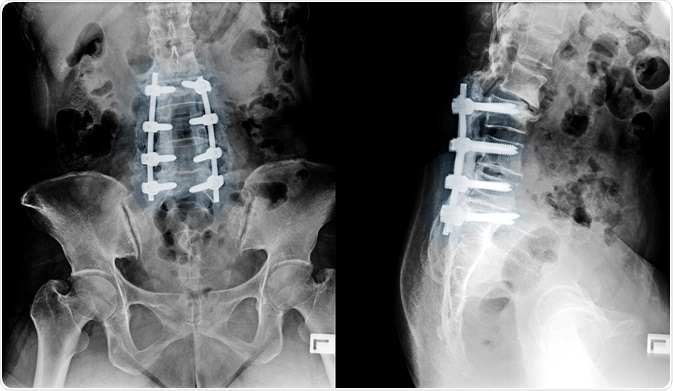

Bioactive glass bone graft

Image credit: Shutterstock | ChooChin